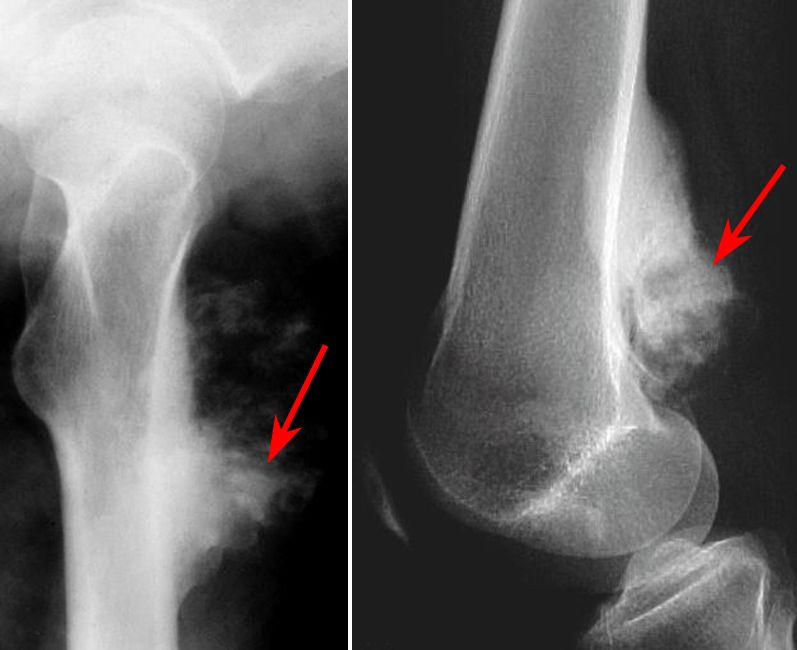

- Рентгеновское обследование является одним из самых эффективных методов диагностики. На снимке специалист, при наличии болезни, обнаруживает так называемый «треугольник Кодмэна», представляющий собой треугольный козырек. Кроме того обнаруживаются игольчатые спикулы;